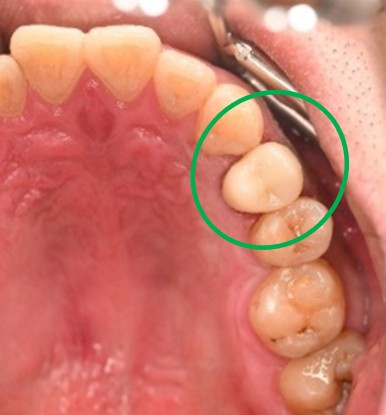

男性 Mさん 50代 (オールセラミック冠)

主訴

右上奥歯が、冷たいものにしみる。

治療内容

歯髄(神経および血管)まで到達する大きな虫歯でしたので、抜髄(歯髄を取り除く)をし、ファイバーコアをいれ、オールセラミック冠を被せました。

所感

現在、保険治療において、限定的ではありますが、大臼歯にも白い被せ物(プラスチック冠)ができるようになりました。しかし、実感としてプラスチック冠は、

- すり減りやすい。割れることがある。

- バイオフィルム(細菌およびそれから産生される副産物の塊)が付着しやすいので、歯周病および2次カリエス(被せ物と自分の歯の境目から再度虫歯になる)になるリスクが高い。

- 変色する。

という点を感じます。白い被せ物が保険の治療でできるという理由で、安易にプラスチック冠を選択し、割れたりすり減ったり、変色したらもう一度被せなおせばいいと考えるのであれば、一度立ち止まって考えてみてください。歯の量は、治療するたびに薄く少なくなり、歯根破折のリスクが高まります。もし大きな虫歯になってしまったら、最高レベルの根管治療をし、最良の被せ物であるオールセラミック冠を被せ、定期的にお口の中のクリーニングをし、同じ歯を2度と治療しないことが、歯を長持ちさせる最良の方法だと考えます。

オールセラミック冠(失活歯):¥104,500(税込)

Before

劣化したプラスチック冠

After